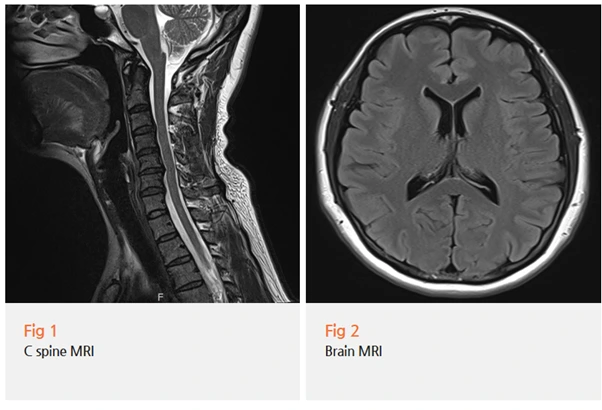

당일 뇌와 경추 MRI를 먼저 진행했습니다.

결과는 예상대로였어요.

경추 4-5-6번 사이에 협착증이 확인됐고, 뇌 MRI에서는 특이 소견이 없었어요.

목의 문제가 머리 찌릿찌릿과 이명, 어지럼증까지 만들어내고 있었던 거예요.